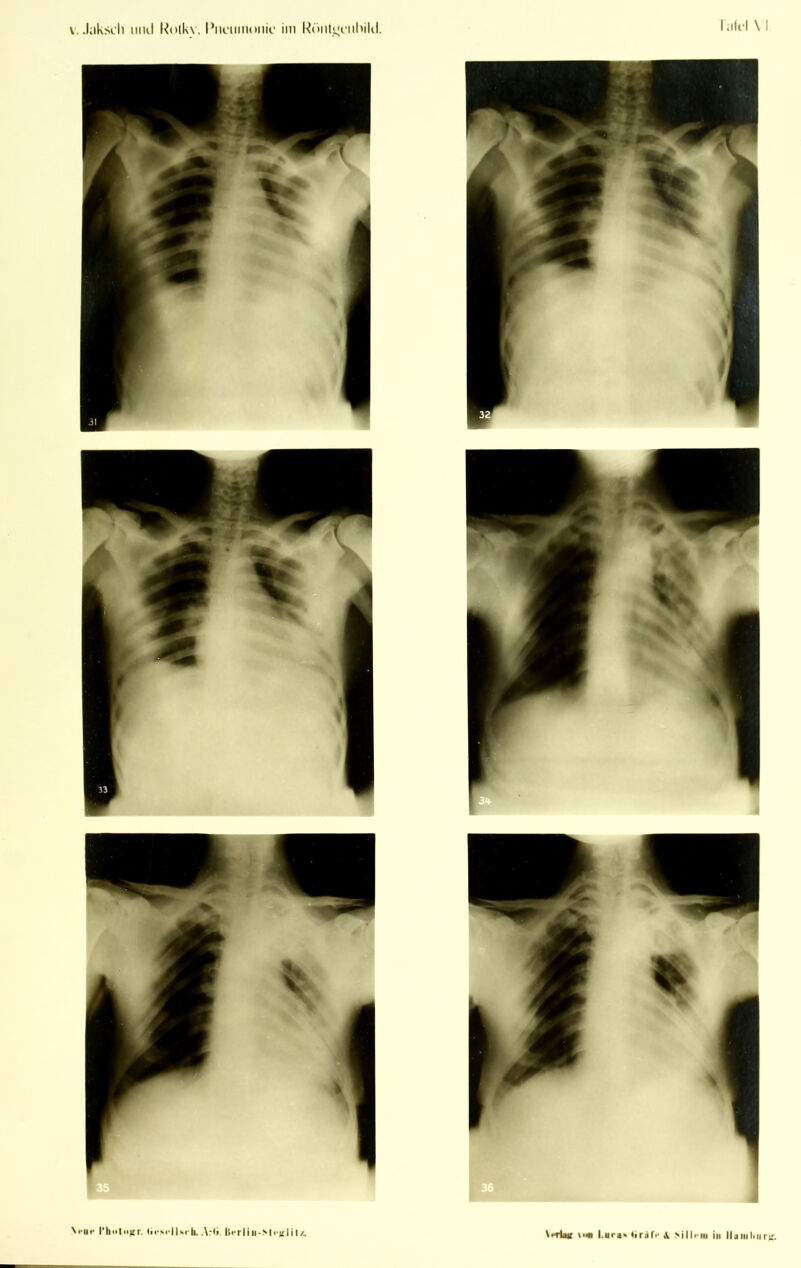

Die Pneumonie im Röntgenbilde ... : mit 59 Röntgenbildern auf 10 Tafeln und 10 Skizzenblättern / von R.v. Jaksch und H. Rotky.

Credit: Die Pneumonie im Röntgenbilde ... : mit 59 Röntgenbildern auf 10 Tafeln und 10 Skizzenblättern / von R.v. Jaksch und H. Rotky. Source: Wellcome Collection.